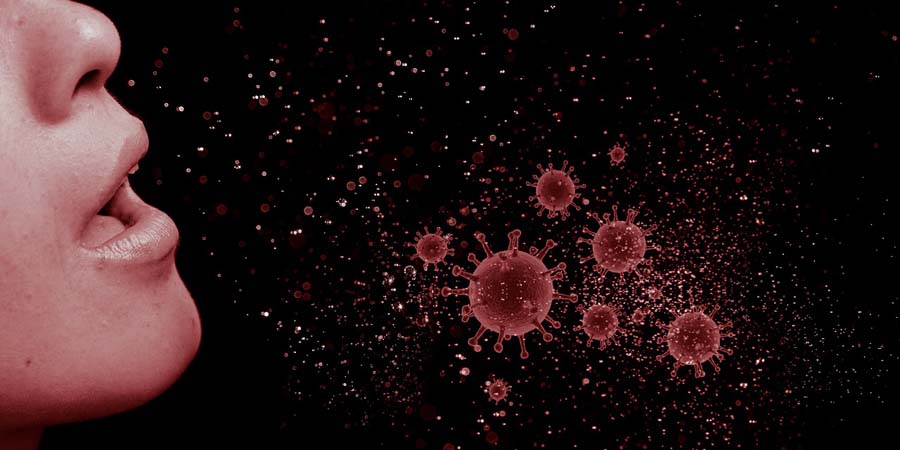

В Саратовской области за сутки выявили еще 247 больных коронавирусом

В Саратовской области за сутки обнаружили 247 зараженных коронавирусом. Об этом сообщается в телеграм-канале «Время Саратовское. Официально».

Общее количество заболевших COVID-19 составляет в регионе 77 913 человек. Выздоровели с начала эпидемии 72 340 человек, за сутки — 220.

По клиническому течению болезни распределение среди вновь выявленных следующее: с пневмонией — 76, с признаками ОРВИ — 165, с бессимптомным течением — 6. С установленным источником заражения — 246, завозные случаи — 1.